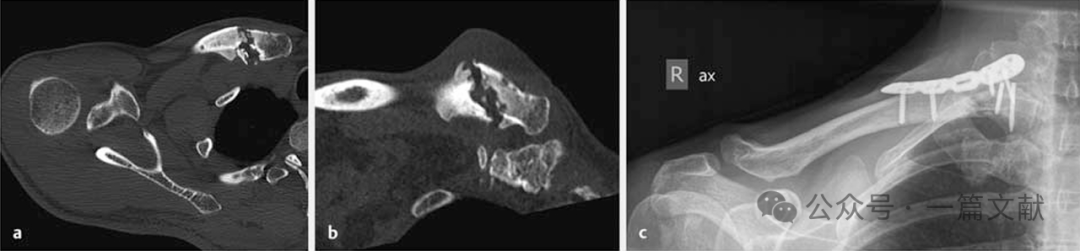

4.1 锁骨骨折的双钢板固定:常用于锁骨骨不连的翻修手术,或锁骨近端骨折的固定。如下图,

锁骨近端骨折术后8周,出现肥大性骨不连,内固定失效。

2.4,2.7mm LCP 双钢板翻修手术,10个月骨性愈合。